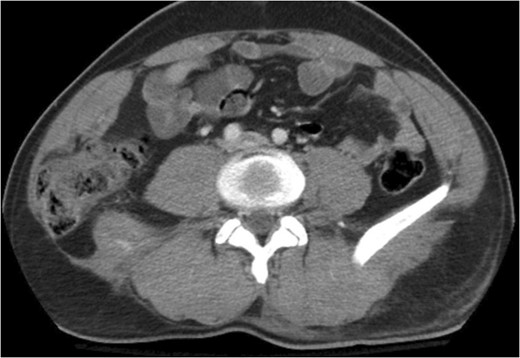

A 43-year-old male patient presented with a right-sided traumatic lumbar hernia after a blunt mechanism. The patient had been pinned between a dirt-mover’s claw arm resulting in a crush mechanism. He sustained injuries to the lumbar spine, sacrum, abdominal wall and 12th rib. On presentation, he did not have clinical or radiographic evidence necessitating abdominal exploration and was observed in a monitored setting. Computed tomography imaging demonstrated a Grynfeltt defect with herniation of the ascending colon and cecum through an area defined by the 12th rib, quadratus lumborum and internal oblique (Figures 1 and 2). After several days of observation and recuperation, the patient continued to have significant pain overlying the hernia site. We electively brought him to the operating room on post-injury Day 4. A laparoscopic repair of the traumatic hernia was performed. Key operative steps included: (i) Wide exposure of the hernia defect via incision of the peritoneum and transversalis as well as mobilization of the ascending colon and duodenal sweep (Figures 3 and 4). (ii) Primary repair of the defect with intra-corporeal suturing of the oblique musculature (Figures 5 and 6). (iii) Placement of an underlay mesh with appropriate redundancy at least 4 cm in all directions around the defect and seating against the iliac crest (Figure 7). Post-operative imaging demonstrates obliteration of the hernia defect and restoration of the abdominal wall (Figures 8 and 9). The patient has recovered, returned to the work force and has no pain or bulge at the repair site 6 months after injury.

With the patient in the left lateral decubitus the herniated right colon spontaneously reduces and the hernia is demonstrated.